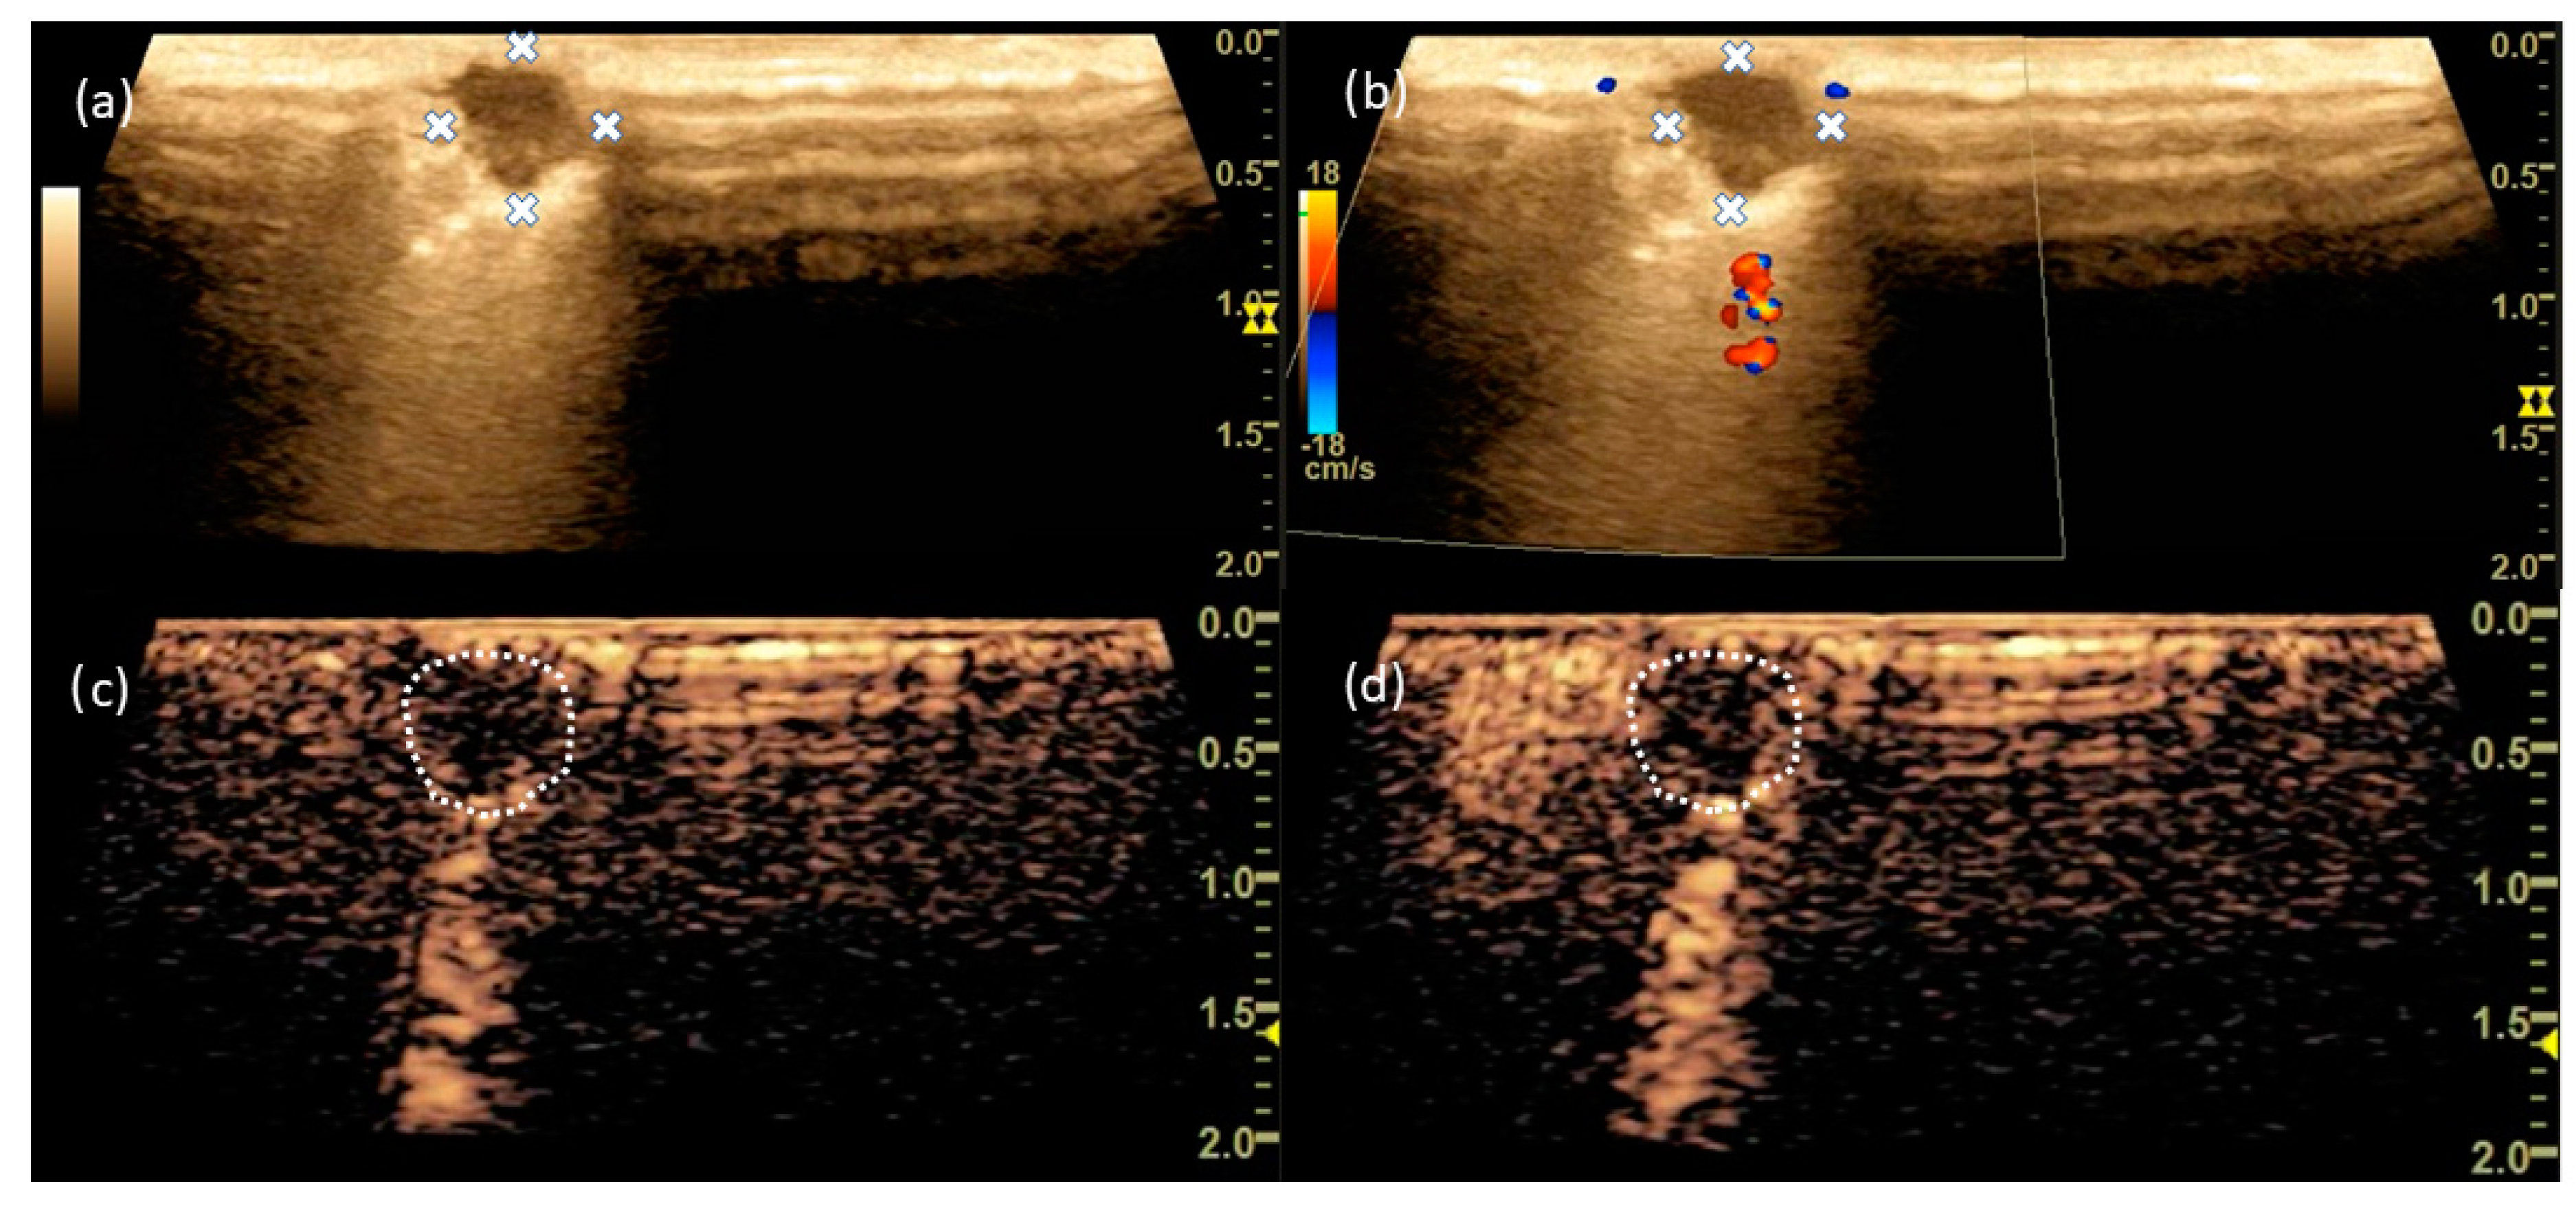

3.6. Case 1

3.7. Case 2